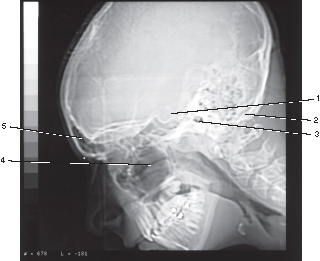

Number 1 corresponds to which of the following?

Posterior clinoid process

Q

Sphenoid sinus